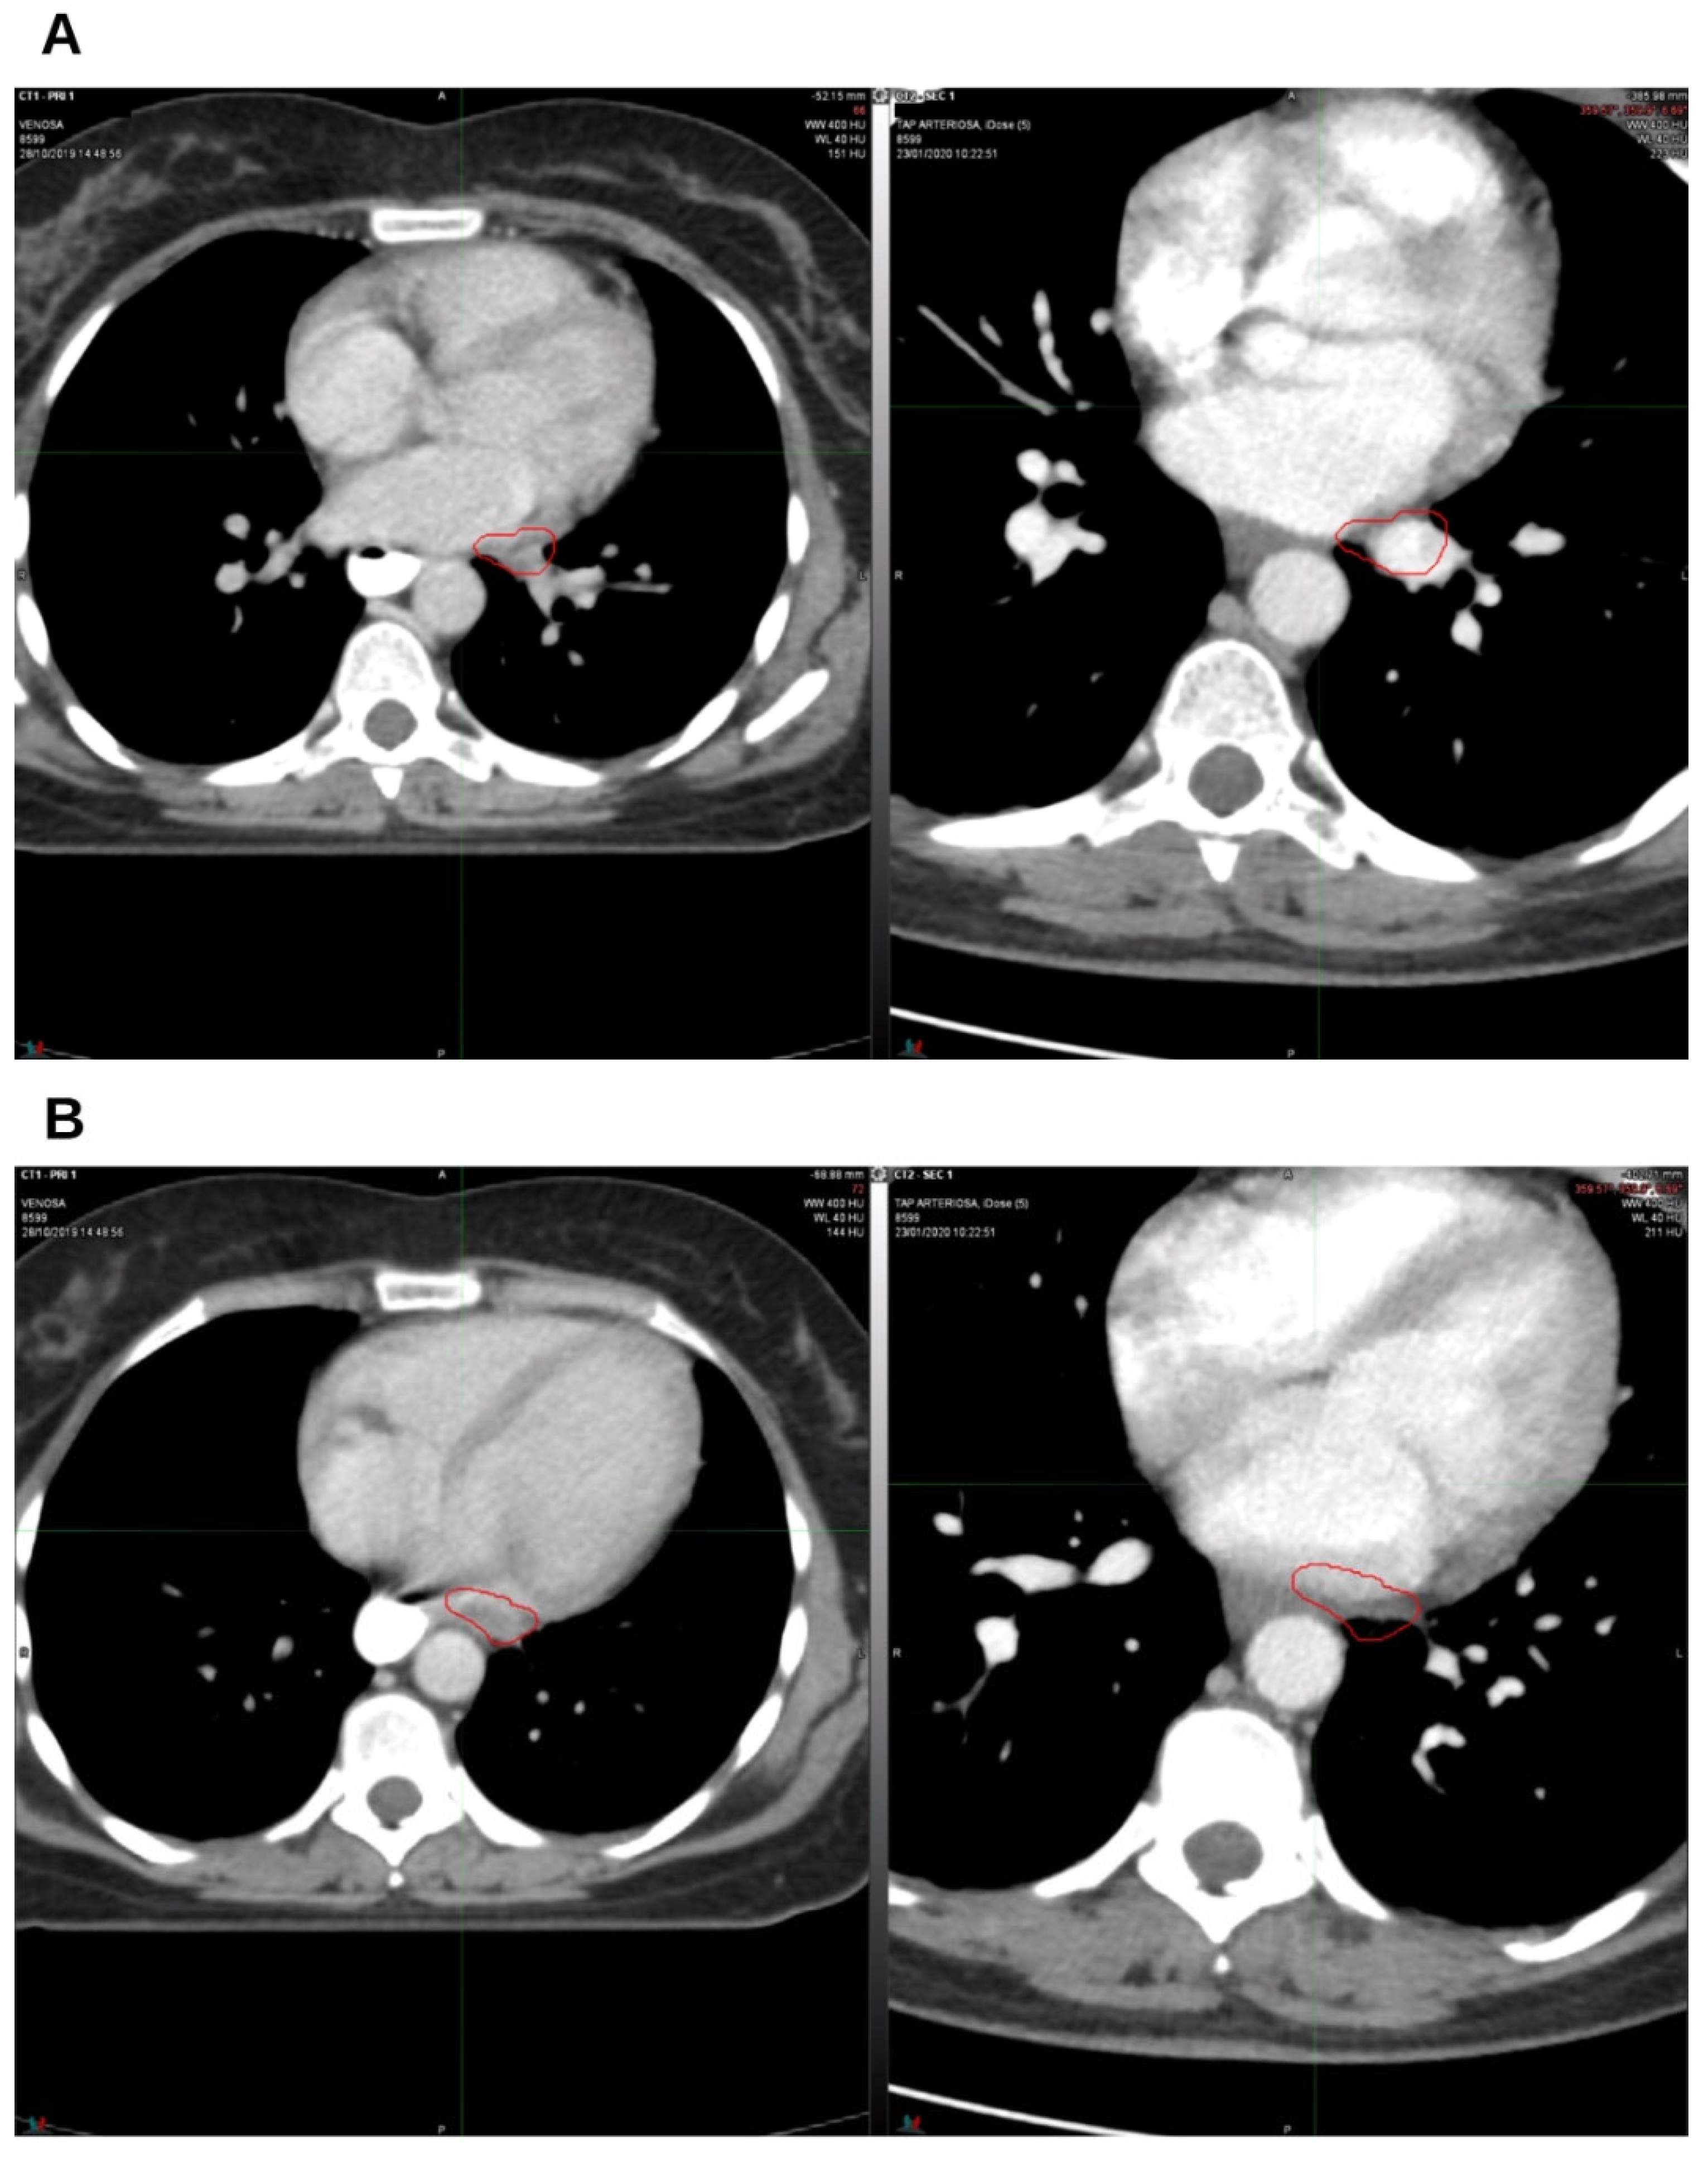

2. Case Presentation